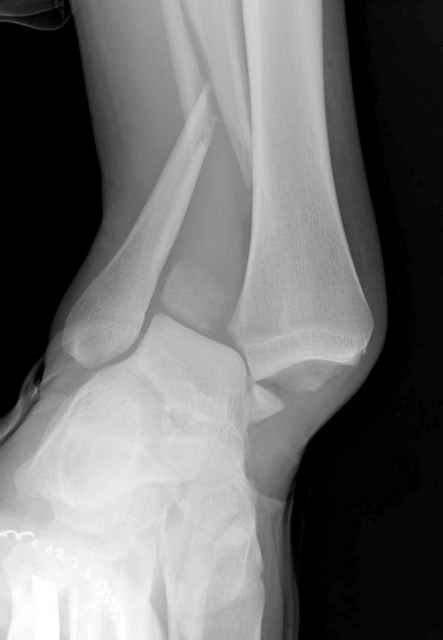

>На сделанных у нас снимках видно, что не все благополучно...

Неравномерность суставной щели может быть связана с разрывом глубокой порции дельтовидной связки и ротацией м/берцовой кости за счет поврежденных структур синдесмоза(репозиция ее на уровне перелома как-будто удовлетворительная).

По моему мнению,ассиметрия суставной щели обусловлена импрессией медиальной части суставной поверхности б/б кости. Да, позиционный винт здесь не лишен, но через 4 недели целесообразность его проведения сомнительна, брейс, ограничение осевой нагрузки достаточно.Есть еще деонтологические аспекты повторной операции, не все так плохо выполнено предыдущим доктором!

Импрессия медиальной части суставной поверхности бывает при супинационном механизме перелома лодыжек (тип А по классификации АО). Здесь механизм пронациия+наружная ротация (тип С, синдесмоз и межкостная мебрана повреждены),

перелом медиальной лодыжки отрывной, при этом в 20-30% бывает повреждение дельтовидной связки.

Клиновидность щели сустава следствие повреждения дельты, невосстановления длины малоберцовой или (хотел сказать "установки в гипсе", но оного, вроде,

нет)? Устранить бы причину. А равно как и тенденцию" к наружному подвывиху. Чрескостный остеосинтез - метод выбора.

Мое мнение, что никакой ротации малоберцовой кости здесь нет и синдесмоз тоже впорядке. Все дело в некачественно репозиции медиального мыщелка. Скорее всего его или немного ротировали при операции или сместили латерально. Более склонен ко второму варианту.

При реконструкции голеностопа, о важности восстановления длины малоберцовой для профилактики пост травматического артроза разбирали в предыдущих дискуссиях. Нарушенную биомеханику голеностопа без восстановления длины малоберцовой, не восстановить только швом медиальной связки.

Расширенная медиальная щель более чем на 4 мм и укорочение малоберцовой более чем 2 мм, а перелом заднего края большеберцовой смещения более 2мм с вовлечением 30% поверхности сустава, считается отходом от нормы голеностопного сустава, и подлежит к оперативному вмещательству.